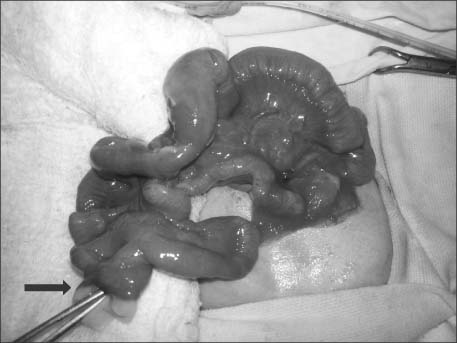

Fig. 1). Meconium could be seen coming from the proximal limb of this Y. Patient was taken up for surgery after adequate hydration. Under general anesthesia, prolapsed loops were approached through circumferential incision and excision of omphalocele membrane. Intestine was delivered outside the abdomen and prolapsed bowel was reduced. A PVID opening was noted in the distal ileum at the site of prolapse (

Fig. 2). It was a wide mouthed PVID from where the ileal loops were intussuscepting and prolapsing outside. The intussuscepting bowel loop was gently reduced. The distal ileal segment with the PVID was resected and an end to end anastomosis of the bowel was done (

Fig. 2Intraoperative picture with arrow and forceps at site of wide mouthed patent vitellointestinal duct from where intussuscepting ileal loops were reduced.